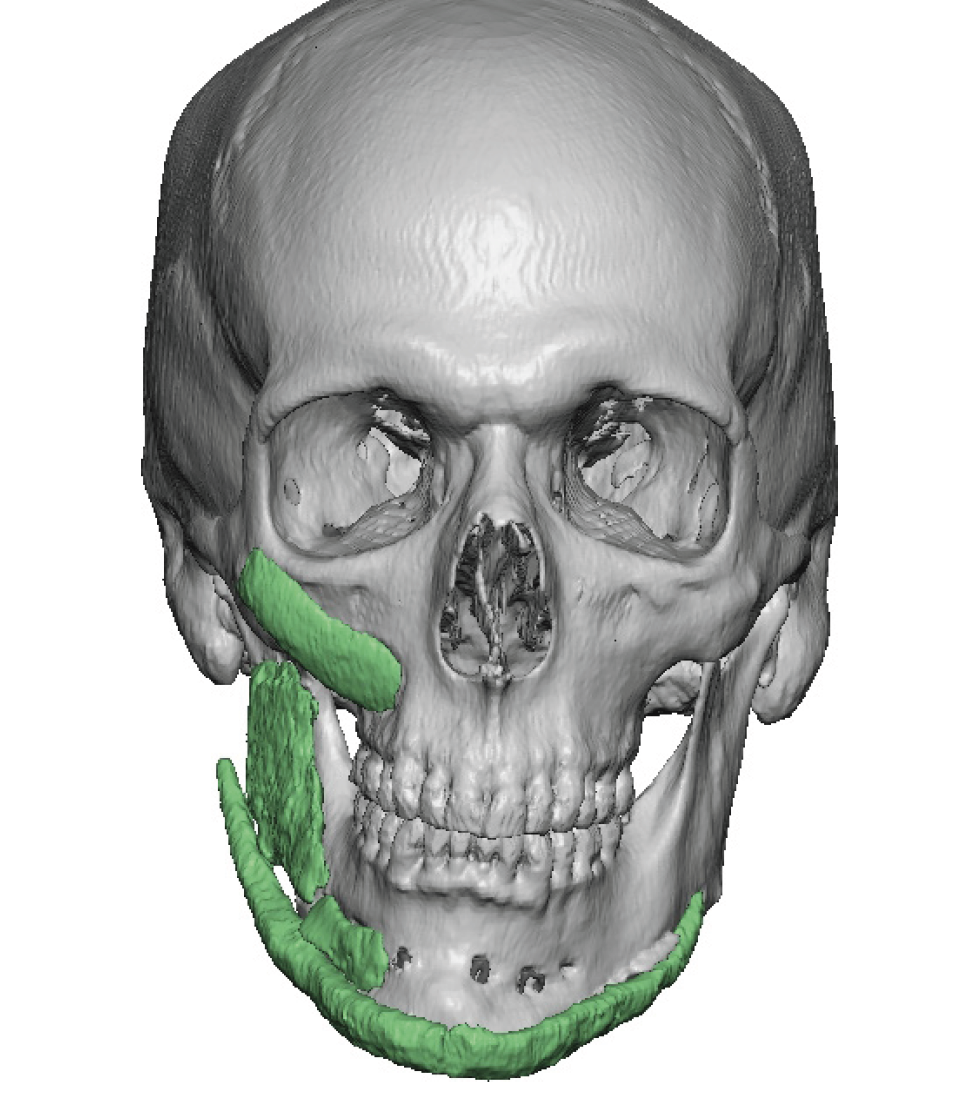

The most common form of facial asymmetry in my experience is right sided and affects the cheek and jawline most significantly. Provided the occlusion is well aligned and stable, or previously optimized with double jaw surgery, implants are the secondary approach to lower facial asymmetries of the cheek and jaw. While implants have been around for a long time of numerous compositions and shapes their historic use in a 2D or ‘eyeball’ approach to placement and facial asymmetry improvement is limited at best and in many cases actually makes the facial asymmetry worse.

Custom designed or 3D jaw implants are the contemporary workhorse in lower facial asymmetry corrections. With modern patient-specific CT-based implant designing virtual planning an be done to design different right and left dimensions, matching the right and left sides of the jawline and centering the chain can be done far more accurately than stock implants ever could. 3D imaging is important because facial asymmetry is a true 3D problem and standard 2D assessment, even with plain x-rays and 2D CT scans, can not fully appreciate the extent of the asymmetries down to the millimeter level.

In treating secondary facial asymmetries in which a 2D approach has been taken to the mplant used and their placement it can be very much an historical adventure. The implants used and their position is known beforehand by the 3D CT scan but unearthing them and digging them out poses it own set of challenges in many cases.

- Facial asymmetry is a multi-dimensional hard and softC tissue problem whose contemporary treatment requires 3D assessment and treatment planning.

- Secondary facial asymmetry surgery will run into prior implant placements and osteotomy fixation hardware which must be considered in the treatment planning.

- Most jaw asymmetries are best treated by a wrap around jawline implant approach to manage the bilateral deformities.

- Cheek flatness/hypoplasia is almost always part of a significant jaw asymmetry.